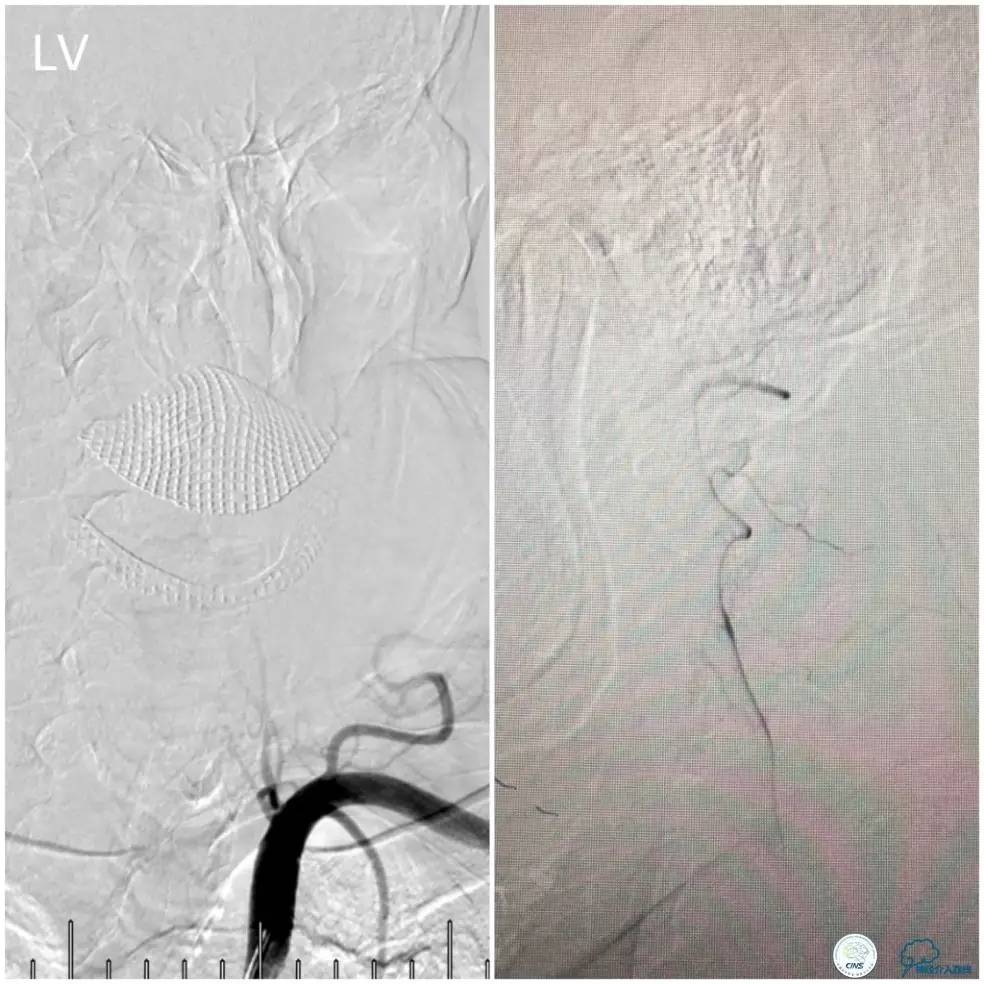

Ultra-Soft球囊(3.0mm×20mm)于狭窄处预扩张后置入EXCEL支架(4.0 mm× 24mm),球扩后造影见支架贴壁良好,远端血管显影好,前向血流TICI3级。6F导引导管沿微导丝通过右椎动脉V1段支架至V2段(图11)。

图11

此时多体外投照显示右椎V4-基底动脉极重度狭窄,几近闭塞(图12)。

图12